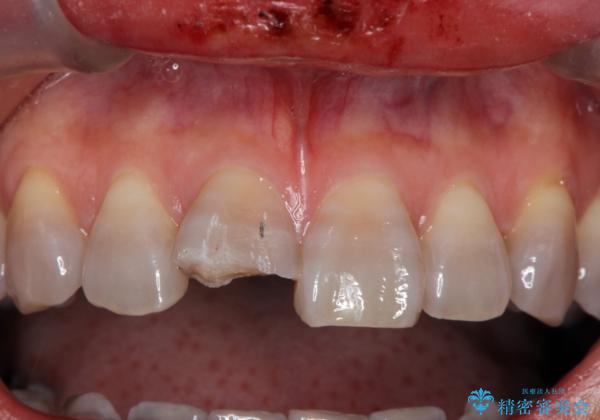

- 転倒し前歯を地面に強打して折れたとのことで来院。

幸い神経は生きており、セラミックでかぶせることになりました。

テトラサイクリン歯といって縞模様の強い歯の色調再現を行いました。

まず保険治療でコンポジットレジン修復を行い、神経の状態を確認した後、クラウンによる修復を行いました。

将来神経が失活する可能性もありますので経過観察する必要があります。